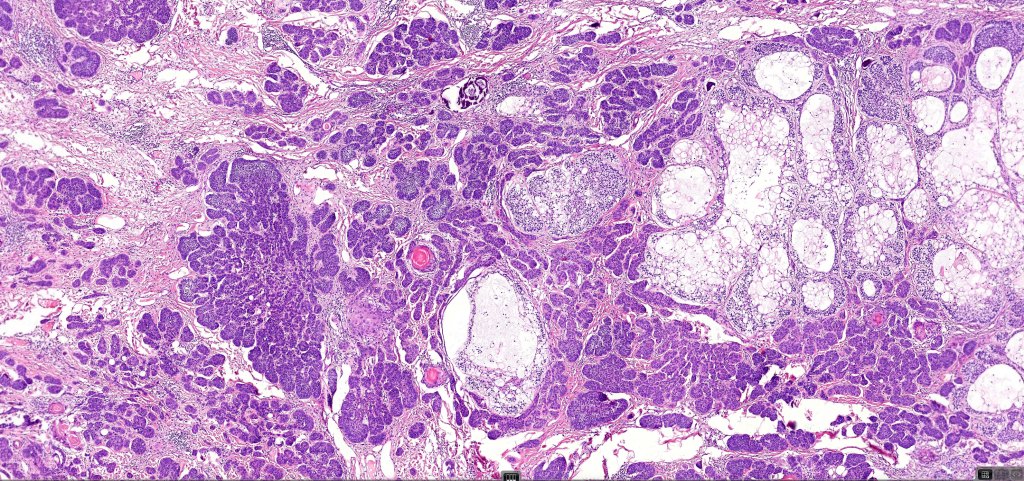

•A wide variety of histological variants are possible including nodular, nodulocystic, ulcerative, superficial, micronodular, infiltrating/infiltrative, keratotic, basosquamous, pigmented, morpheaform, keloidal, clear-cell, signet-ring cell & granular cell variants, BCC with monster cells, BCC with metaplastic features, BCC with matricial differentiation, basomelanocytic tumor (see separate blog), BCC with thickened basement membrane, BCC with carcinoid-like nuclear palisading & these are illustrated below

•The epithelial component is composed of uniform small, basophilic devoid of desmosomes

•Peripheral palisading

•Retraction artifact with stromal mucin

•Pseudoglandular appearance